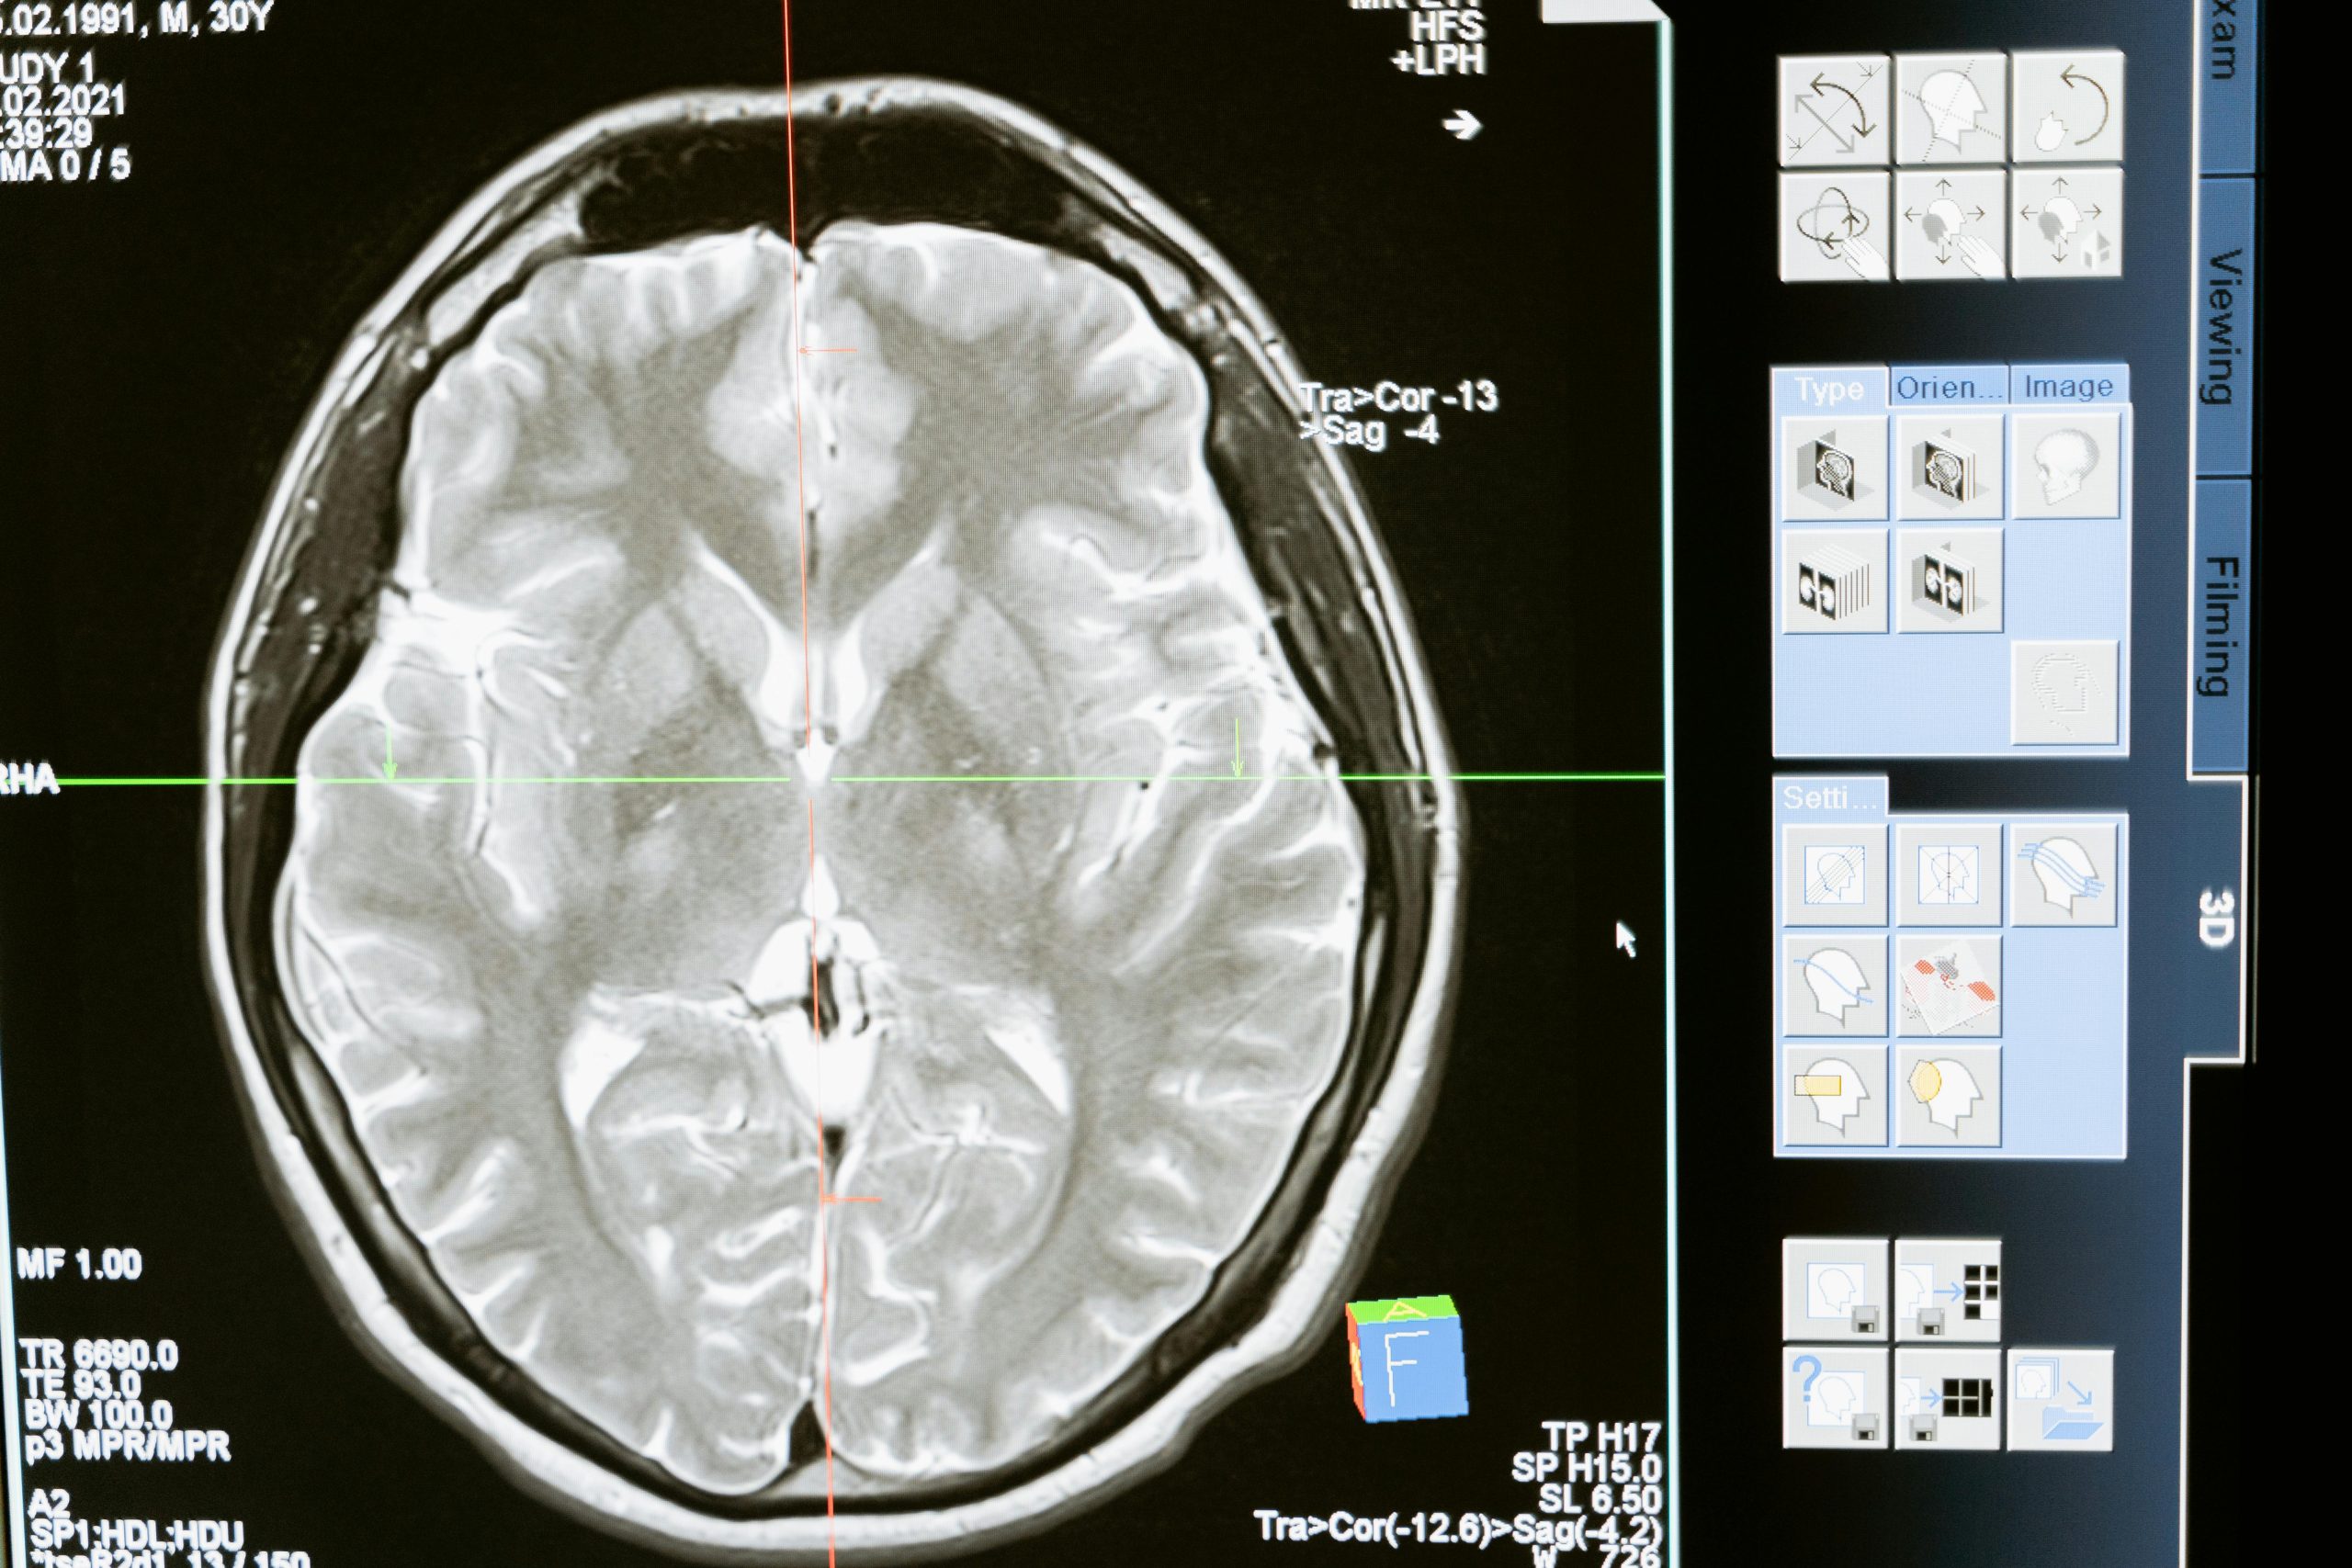

The Limits of Structural Imaging

Conventional imaging retains obvious importance in acute management. However, structurally normal scans do not answer functional questions. Network integrity, processing efficiency and executive regulation are not directly visualised on routine CT or MRI.

An absence of visible lesion does not equate to intact cognitive performance. Nor does the presence of a focal abnormality automatically dictate outcome. Contemporary neuropsychological understanding emphasises complexity and interaction rather than simplistic localisation.

For advocates, overreliance on radiological reassurance risks oversimplification.